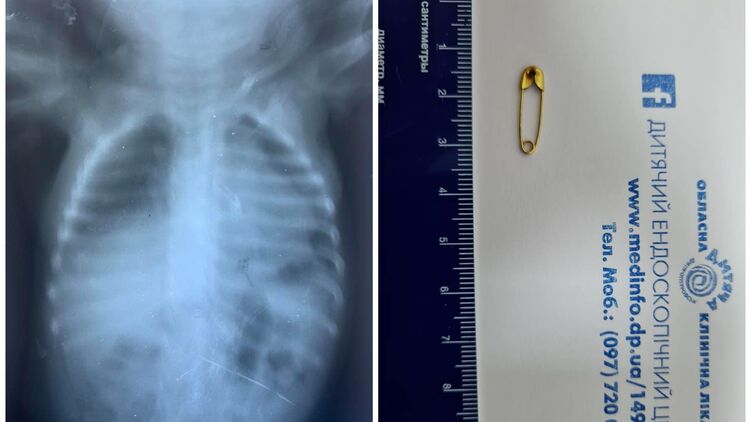

Рентген показал наличие инородного тела в организме грудничка. Фото: Facebook

Малыш, которому нет и годика, вдохнул булавку во время игры. Ребенку провели дополнительное обследование. После чего под общим обезболиванием при проведении бронхоскопии извлекли инородное тело.